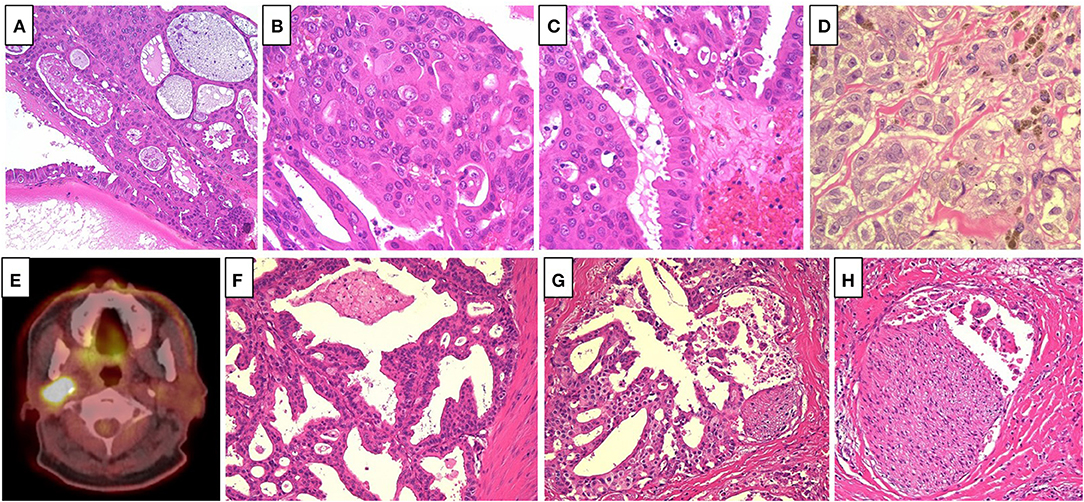

A 65-year old man noticed a cutaneous nodule on his left forearm, which had gradually grown. He had a medical history of diabetes mellitus and hypertension. The cutaneous nodule was resected, and was diagnosed to be malignant melanoma. He was referred to our hospital, and underwent wide resection with left axillar lymph node (LN) dissection. The surgical margin of the primary tumor was negative, and one out of the 11 dissected LNs showed metastases. 1 year after the surgery, computed tomography (CT) revealed a nodule in the right parotid gland. The nodule was resected, and histological analyses revealed multiple cysts of various sizes lined by cuboidal, eosinophilic cells with mild to moderate atypia (Figures 1A–C). The cyst lumen contained eosinophilic materials, and some of the cuboidal cells showed decapitation secretion (Figures 1A–C). There were no myoepithelial cells around the luminal cells. In some parts, the tumor cells showed microinvasion. From these findings, a diagnosis of cystadenocarcinoma was made. 4 months after the resection, a nodule with cystadenocarcinoma recurred in the right parotid gland, and right superficial parotidectomy was performed. The surgical margin was negative, and the patient received postoperative irradiation with 60Gy. At 4 and 6 years after the parotidectomy, resection was performed on two cutaneous nodules with metastatic melanoma that appeared on the left forearm (Figure 1D). PD-L1 expression level was <1%, and BRAF mutations were not detected. 9 years after the parotidectomy, positron emission tomography (PET)-CT revealed a 40 × 40 mm mass in the deep lobe of the right parotid gland with high fluorodeoxyglucose (FDG) accumulation (Figure 1E). In addition, multiple small nodules appeared in the lung. The mass in the parotid gland was resected, and histological analyses revealed multiple cysts with frequent papillary projection consisting of a proliferation of cuboidal cells with pleomorphism, indicating recurrent cystadenocarcinoma (Figure 1F). Tumor nests had invaded into the fibrotic stroma and multiple perineural invasions were also observed (Figures 1G,H). Because the mass had extended widely, it could not be completely excised and large parts of the surgical margin remained positive. 8 months after the last surgery, PET-CT revealed an irregularly shaped mass with high FDG accumulation below the surgical wound of the parotid gland (Figure 2A). In addition, right upper deep cervical LNs also showed high FDG accumulation (Figure 2B), indicating local recurrence and cervical LN metastases of cystadenocarcinoma. The size and number of lung nodules had also increased (Figures 2C,D). Because the lung nodules and the mass of recurrent cystadenocarcinoma appeared simultaneously, the nodules may be lung metastases of the cystadenocarcinoma. However, the lung nodules were also suspected to be metastatic melanoma because of the patient's medical history of lymph node and multiple skin metastases of melanoma. The patient would not agree to proposed partial lung resection for histological examination of the nodules. Therefore, based on our suspected diagnosis of lung metastases of melanoma, we proposed treatment with either anti-PD-1 antibody monotherapy or nivolumab and ipilimumab combination therapy. He selected the combination therapy, and was treated with combined nivolumab (80 mg/body) and ipilimumab (3 mg/kg) therapy. 2 weeks after the first administration of these antibodies, he developed Grade 4 liver injury, which required cessation of the treatment and a high-dose oral steroid with mycophenolate mofetil followed by steroid pulse therapy for improvement of the liver injury. However, PET-CT 4 months after the single course of the combination therapy showed that the FDG accumulation of both the mass below the surgical wound of the parotid gland and the cervical LNs had disappeared (Figures 2A,B). In addition, all of the lung nodules had disappeared (Figures 2C,D), suggesting that the combination therapy induced CR. At 10 months' follow-up after the immune checkpoint inhibitor (ICI) treatment, there was no recurrence.

Figure 1. (A) Multiple cysts of various size lined by cuboidal, eosinophilic cells, which contained eosinophilic materials (Hematoxylin and eosin [HE], ×40). (B) The tumor cells showed mild to moderate atypia (HE, ×400). (C) Some of the tumor cells showed decapitation secretion (HE, ×400). (D) The cutaneous nodules revealed proliferation of large atypical epithelioid cell with melanin pigmentation, suggesting metastatic melanoma (HE, ×400). (E) Positron emission tomography-computed tomography revealed a mass in the deep lobe of the right parotid gland with high fluorodeoxyglucose accumulation. (F) Multiple cysts with frequent papillary projection consisting of the proliferation of cuboidal cells with pleomorphism (HE, ×200). (G,H). Tumor nests invaded into the fibrotic stroma, and multiple perineural invasions were also observed (HE, ×200).